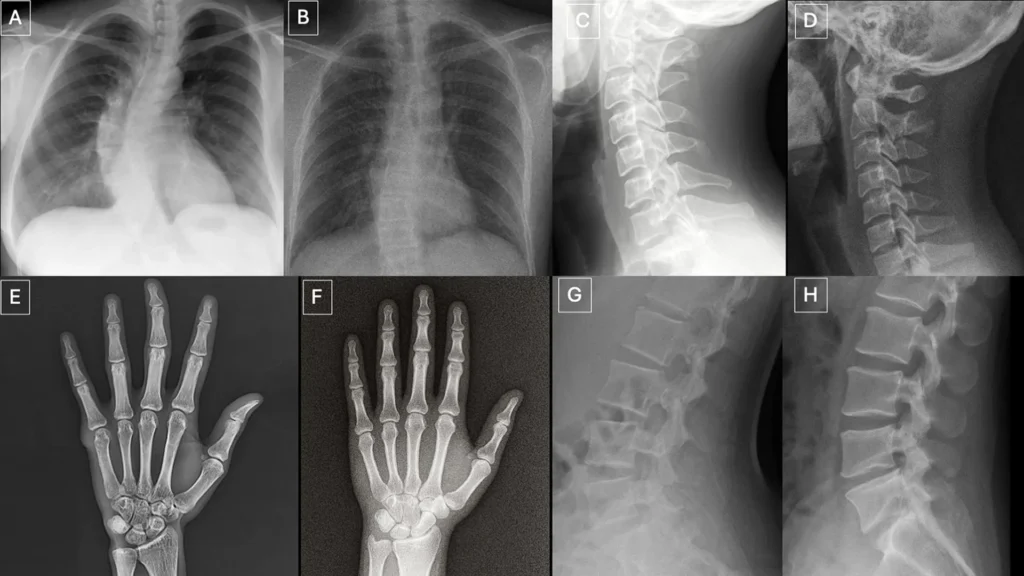

Pistas Visuais em Raios-X Deepfake

Os pesquisadores identificaram vários padrões que podem aparecer em imagens sintéticas.

“Imagens médicas deepfake geralmente parecem perfeitas demais,” disse Dr. Tordjman. “Os ossos são excessivamente lisos, as colunas são artificialmente retas, os pulmões são excessivamente simétricos, os padrões dos vasos sanguíneos são excessivamente uniformes, e as fraturas parecem incomumente limpas e consistentes, muitas vezes limitadas a um lado do osso.”